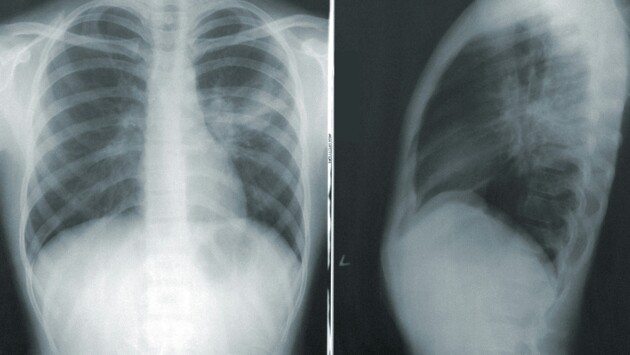

Но ведь опухоль на первой и второй стадии может достигать размеров от 3 до 6 см. Это достаточно большие опухоли, неужели их не видно на рентгене или флюорографии на этих стадиях?

— Их видно. Проблема заключается в том, что размер опухоли — это только часть проблемы. Вторая и третья части — это распространение опухоли и ее гистологическая структура, наличие метастазов. Размер опухоли напрямую коррелирует с распространенностью. То есть чем больше размер опухоли, тем чаще мы встречаемся с наличием отдаленных метастазов.

Поэтому общее правило для всех онкологических заболеваний — не дожидаться, когда опухоль достигнет больших размеров, а выявлять эту опухоль на предельно ранних стадиях. И вот с этим в рентгенографии очень большая проблема: найти маленький, сантиметровый или даже иногда двухсантиметровый одиночный очаг в легочной ткани очень сложно. И даже самые современные аппараты часто не позволяют точно и своевременно это сделать. Это не значит, что найти маленький очаг на рентгенограмме невозможно, но это скорее исключение, чем правило.

Это подтверждают исследования ученых РМАНПО, НМИЦ онкологии им. Блохина, Российского биотехнологического университета и компании «АльфаСтрахование-ОМС». Согласно данным исследования, рентгенография и флюорография органов грудной клетки совсем не «видят» рак легкого на первой стадии, пропускают большинство случаев рака легкого на второй стадии и половину случаев на третьей. С помощью обычной рентгенографии не удалось достоверно определить признаки рака легкого на ранних стадиях в 84,3% случаев. Вероятно, из-за неэффективности такой диагностики одногодичная летальность с момента установления диагноза «рак легкого» в два раза превышает данный показатель у онкологических пациентов.

— Нет, рак легкого можно и необходимо выявлять при рентгенографии. Сегодня именно так и происходит в обычной практике. Но мы говорим о суперранней диагностике, когда размеры очага в легком не превышают 1–2 см. Именно такие одиночные очаги труднее всего заметить на рентгеновском снимке. Для более крупных образований рентгенография — вполне надежный метод диагностики. Нельзя забывать, что во второй половине прошлого века она сыграла колоссальную роль в ранней (по тем представлениям) диагностике заболеваний органов дыхания, будь то рак легкого или туберкулез. Вся система раннего выявления этих заболевания в позднем СССР была основана именно на проверочной флюорографии.

При этом сегодня есть способ, который может существенно улучшить диагностику рака легкого на гораздо более ранней стадии — это низкодозная компьютерная томография (НДКТ). Ее внедрение в профилактические мероприятия позволит увеличить выявляемость рака легкого на ранних стадиях в два-три раза.